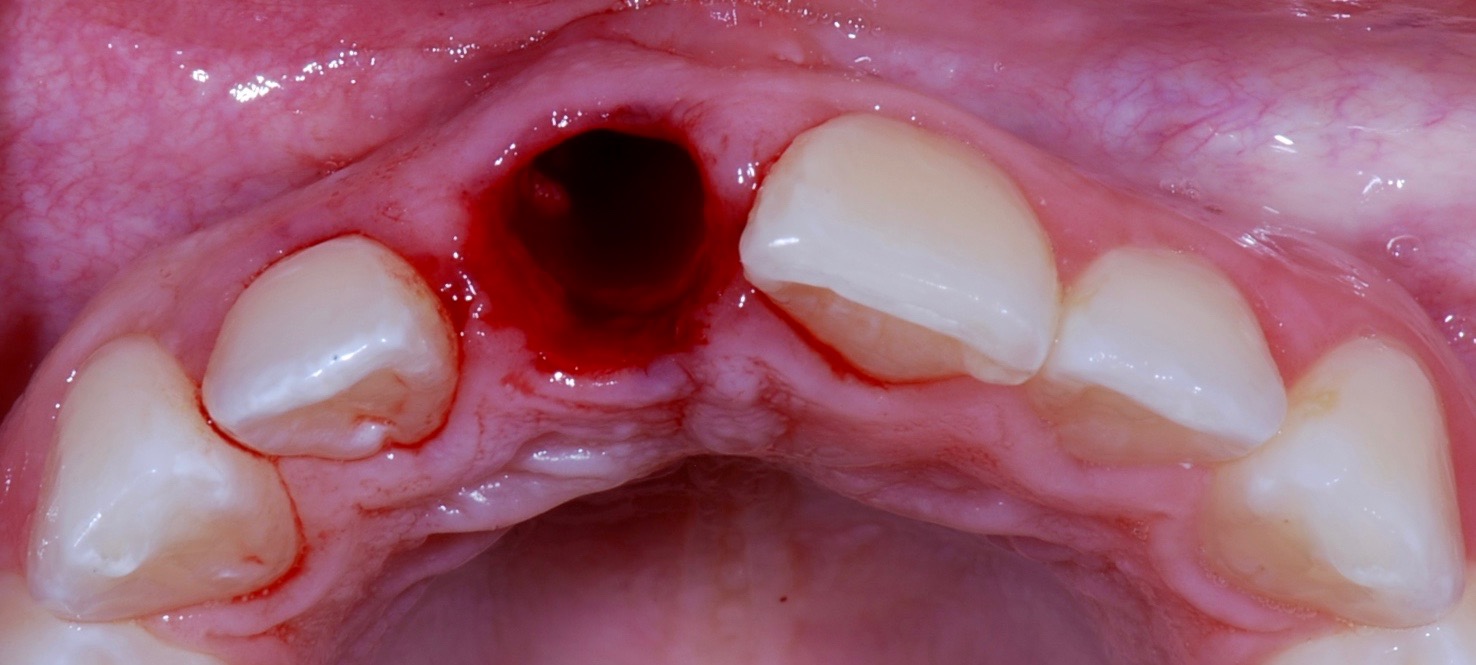

Plugging into digital workflows provides opportunities to integrate CAD/CAM technologies at every step of the treatment process for dental implants. In another example, a patient presented with a failing tooth No. 8 (Figure 6 and Figure 7). After discussing treatment options, the patient chose to forgo any treatment to address tooth and soft-tissue asymmetries and wanted to proceed with a dental implant-supported restoration without additional treatment. After integrated 3-dimensional planning, the tooth was extracted, and then an implant and the final custom CAD/CAM abutment (titanium base with zirconia supra-structure) were placed with a provisional restoration in the same visit (Figure 8 and Figure 9). Soft-tissue grafting was also done at the same visit to address the deficient buccal tissue height on No. 8 (Figure 10). At 3 months, the patient presented for the final restoration, with excellent healing around the implant (Figure 11) and soft-tissue healing guided by the custom abutment (Figure 12).

Fig 8. Extraction site No. 8 after atraumatic removal of the tooth.

Figure 8